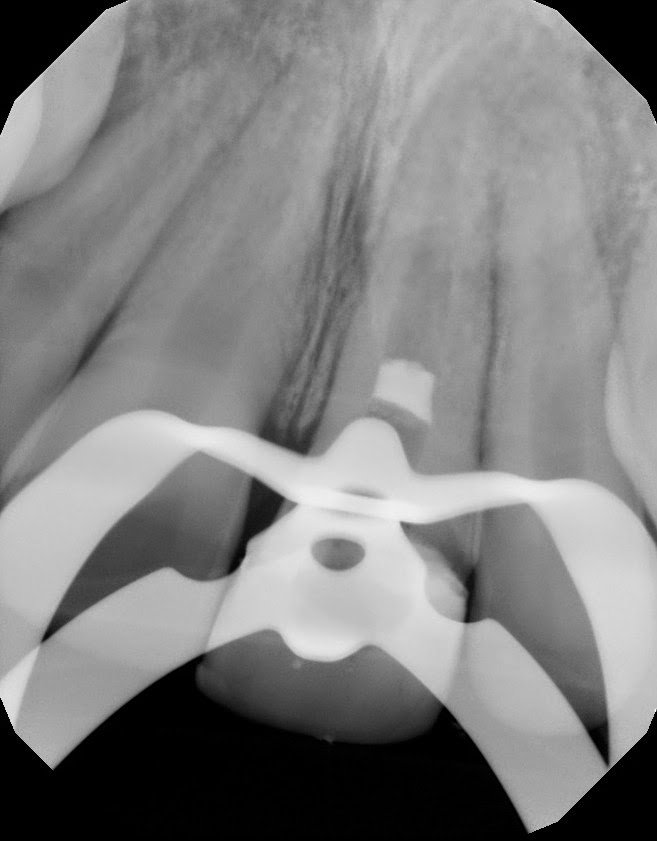

This 8 yr old patient had trauma 3 yrs earlier on this immature #9. His dentist bonded it the best he could. 3 yrs later, the tooth is necrotic with symptomatic apical periodontitis. (non-responsive to cold, pain to percussion, normal probings) Root apex is >1mm open. Pulpal regeneration was recommended.

Pulpal regeneration peformed. Canal debrided with minimal filing, NaOCl irrigation, Saline rinse, EDTA final rinse. Blood clot initiated with MTA coronal plug placed below CEJ (to prevent staining).

Regenerative procedure completed in single step with MTA plug and resin coronal access filling.